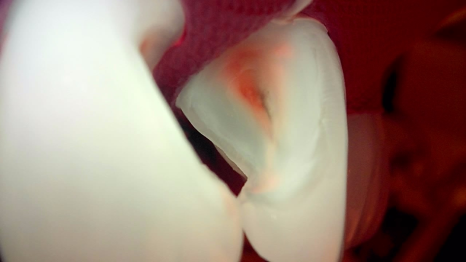

기존 레진을 제거하려고 혹시 떨어질까 싶어 기구로 살짝 만져봤는데 예상대로 바로 떨어나가졌습니다.

이런 형태가 사실.. 탈락이 굉장히 잘 되거든요^^;

그동안 꽉 막힌 레진 때문에 잇몸이 얼마나 답답하고 불편하셨을지 제 마음도 참 좋지 않았습니다.

잇몸이 숨을 쉬지 못해 질식하고 있는 것과 다름없었으니까요.

촬영일 : 251230

불완전한 경계 부분으로 충치도 새로 생겨 큐레이로 계속 확인하면서 충치를 제거해 줬습니다.

그 후 레진 빌드업 단계에 들어갔는데요.